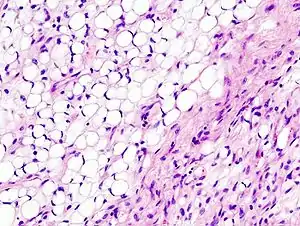

| Histopathologic image of myxoid liposarcoma arising in the deep soft tissue of the thigh. H & E stain. | |

.JPG.webp) Micrograph of myxoid liposarcoma. H&E stain Micrograph of myxoid liposarcoma. H&E stain